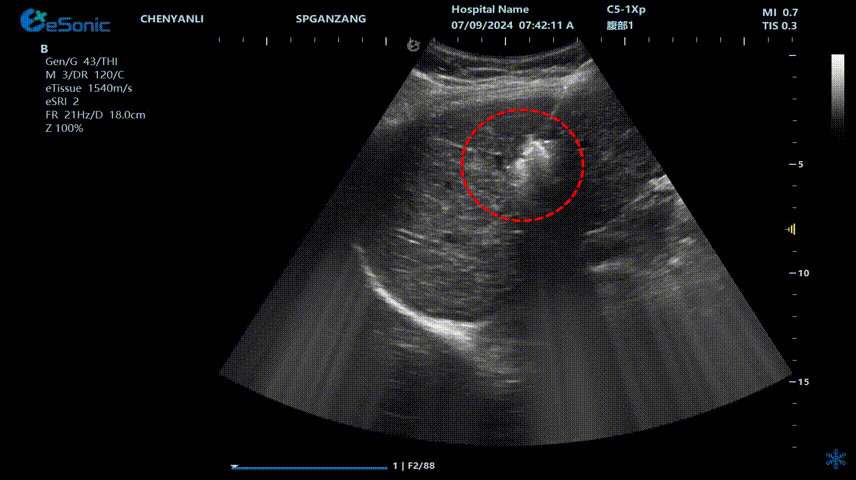

640 (1) (2).gif

肝癌射频消融动态视频

红圈为病灶位置

肝癌射频消融:全麻下彩超探头引导射频针分别植入肝右叶两个稍高回声结节,固定消融,至结节全部为强回声覆盖,覆盖良好,缓缓灼烧针道后退针。